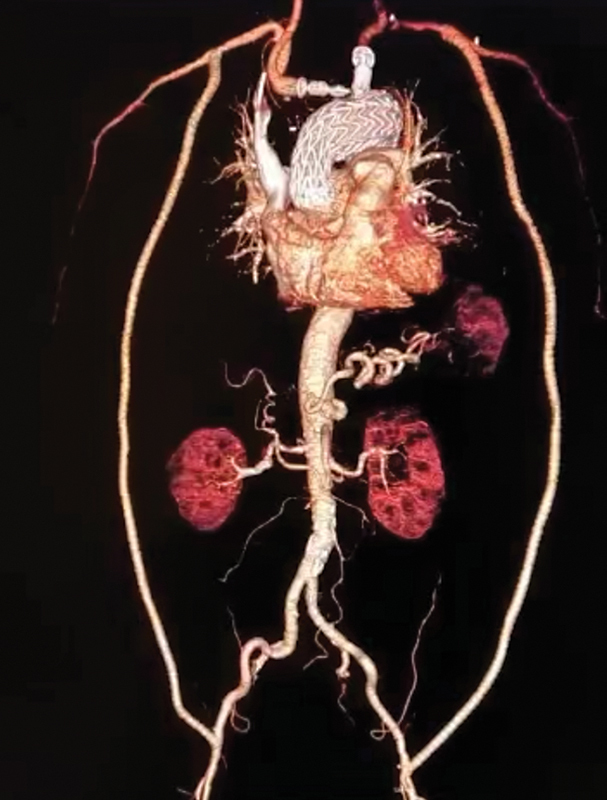

假性动脉瘤的发生会随着原始手术后时间的推移而增加,发生率为 0.2% 至 25%。腋股旁路用于治疗选择性主动脉髂阻塞。腋股动脉旁路术很少反向使用,而且总是用于治疗闭塞性动脉疾病。我们报告了一例吻合口旁主动脉弓假性动脉瘤,并在文献中补充了一种成功的混合治疗方法,即双侧股腋旁路术、所有主动脉上干血栓排除术和主动脉弓内膜覆盖术。

The development of pseudoaneurysms increases with time since the original operation, with incidence 0.2 to 25%. The axillofemoral bypass is employed to treat selective aortoiliac obstructions. Rarely, it is used in reverse form and always for treatment of occlusive arterial disease. We report a para-anastomotic aortic arch pseudoaneurysm and add to the literature a successful hybrid treatment, with bilateral femoroaxillary bypasses, thromboexclusion of all supra-aortic trunks, and aortic arch covering with an endograft.